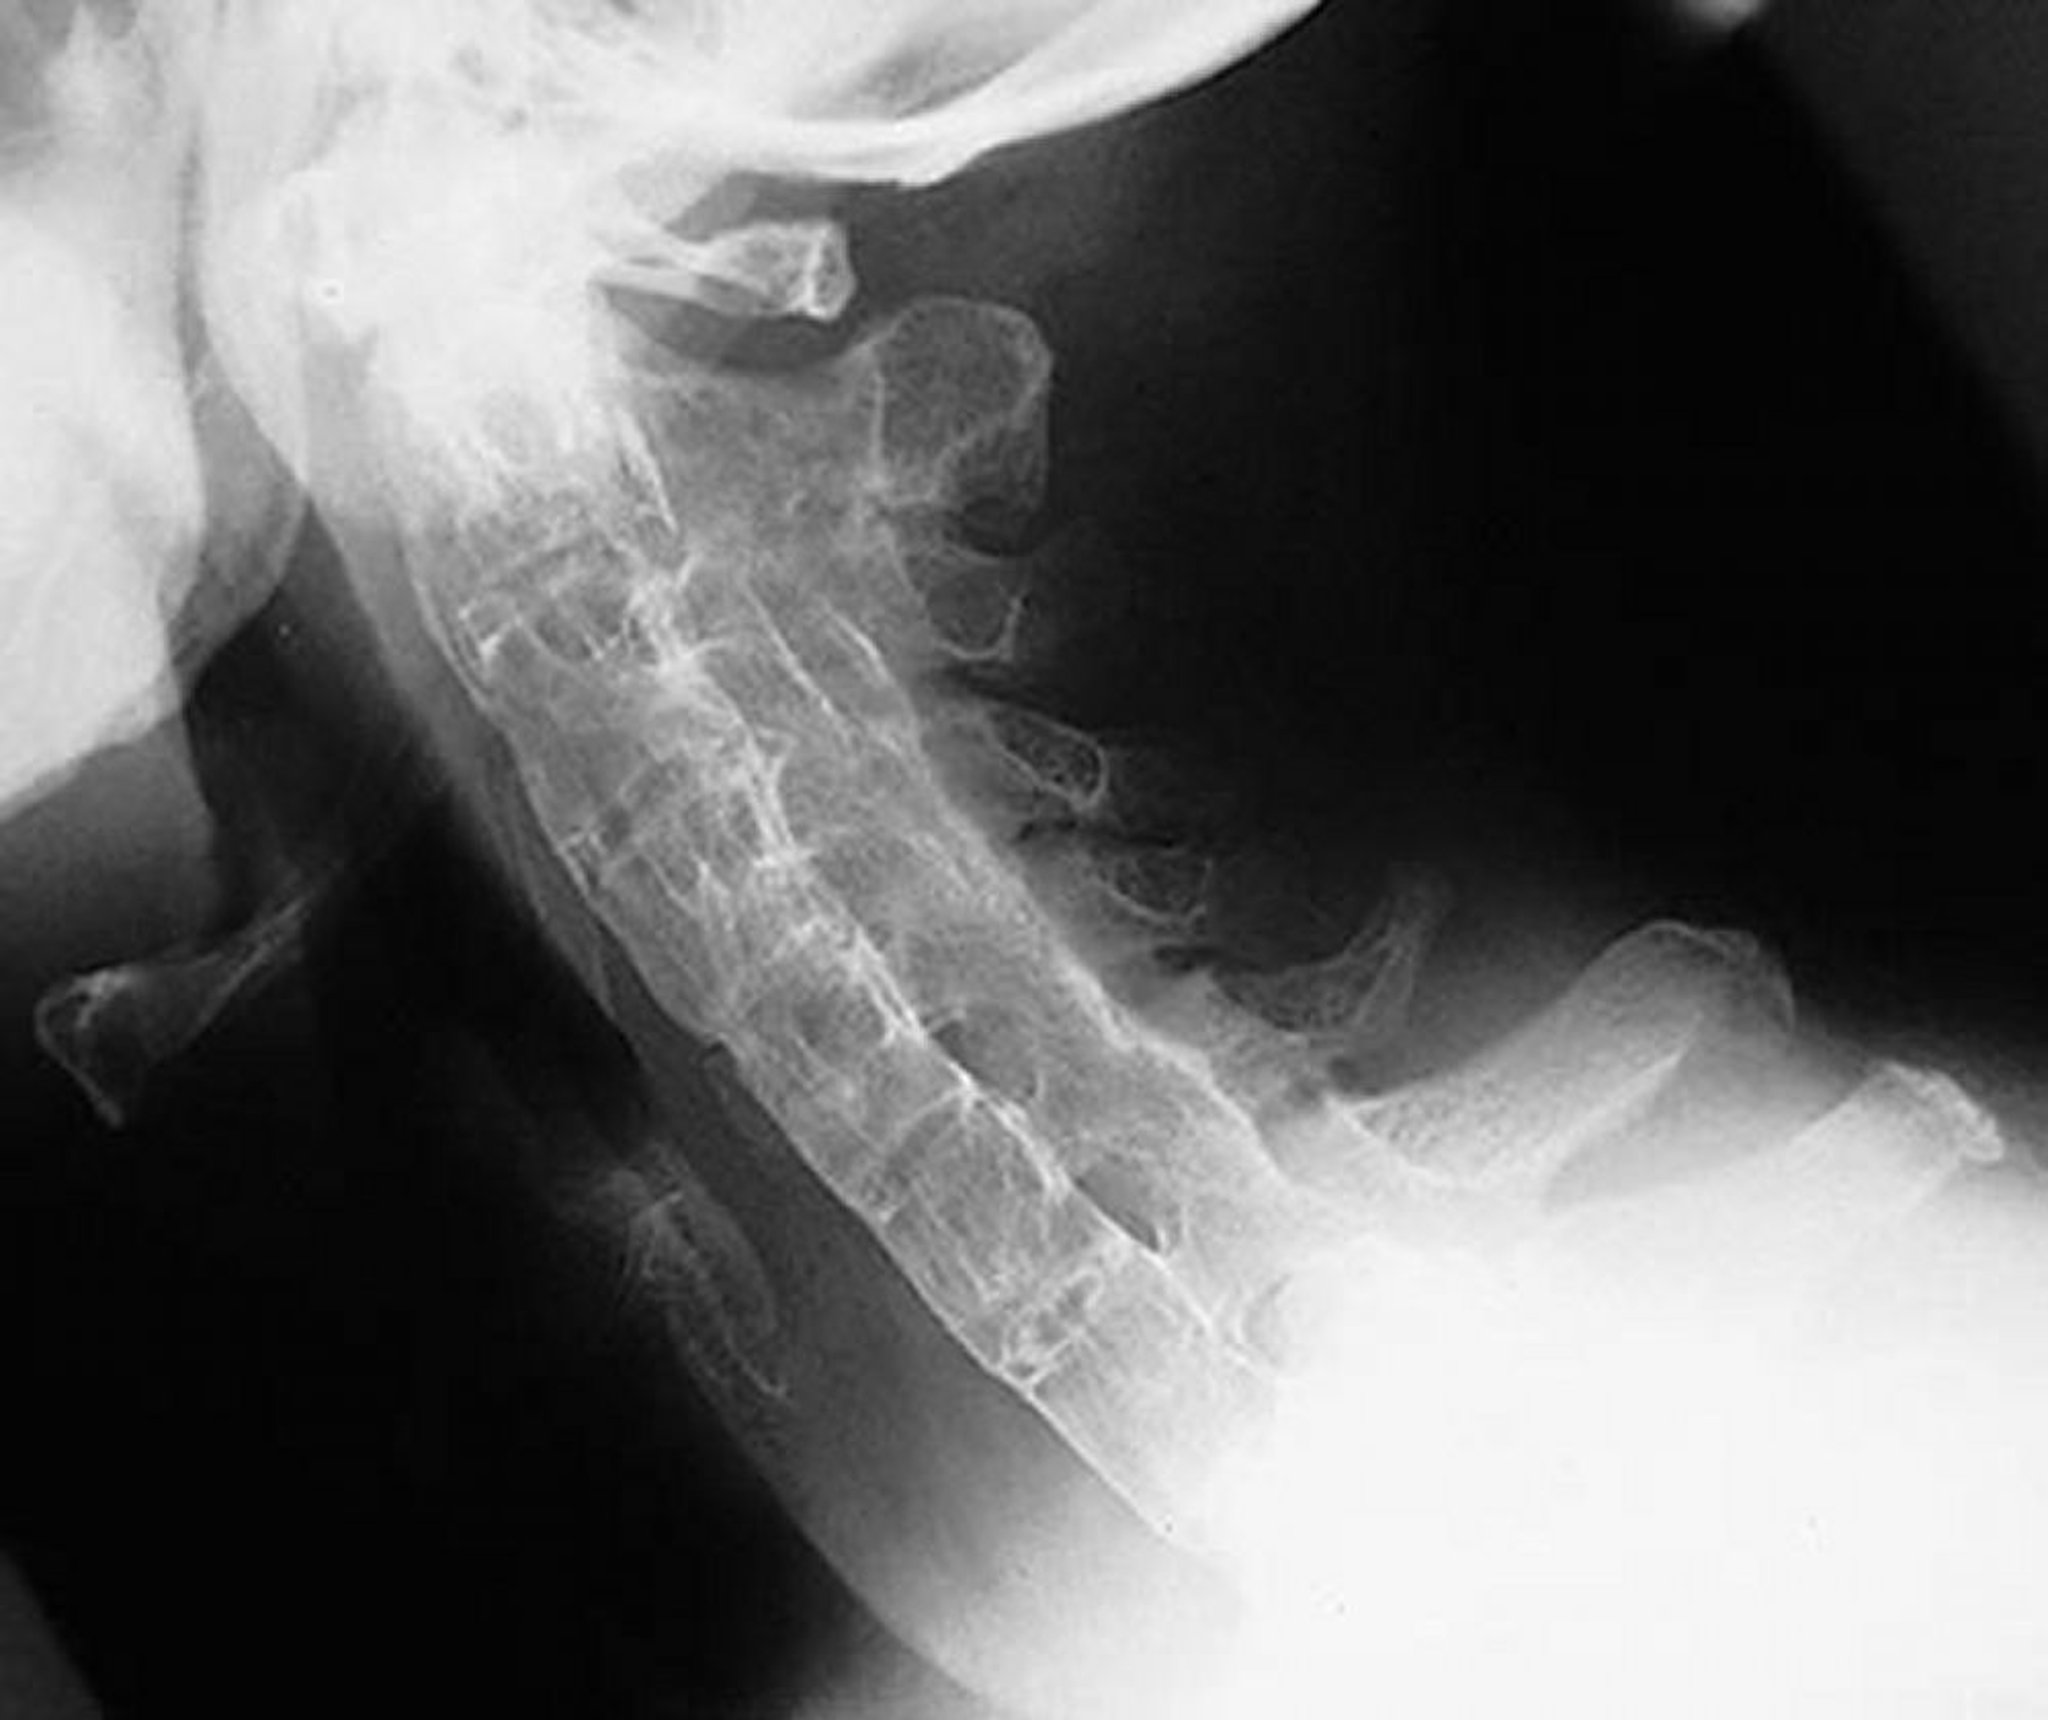

Coluna em bambu na espondilite anquilosante

Essa incidência lateral da coluna cervical mostra uma coluna cervical rígida em um paciente com espondilite anquilosante grave e de longa duração. A coluna vertebral está completamente anquilosada (“coluna em bambu”) decorrente de sindesmófitos, fusão das articulações facetadas (apofisárias) e calcificação ligamentar paraespinal.